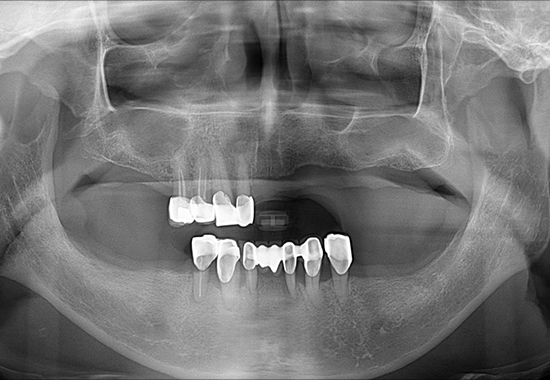

BEFORE

- 식립 개수 : 15개 (상악 9개 하악 6개)

- 수술 내용 : 교합 거상, 크라운, 임플란트